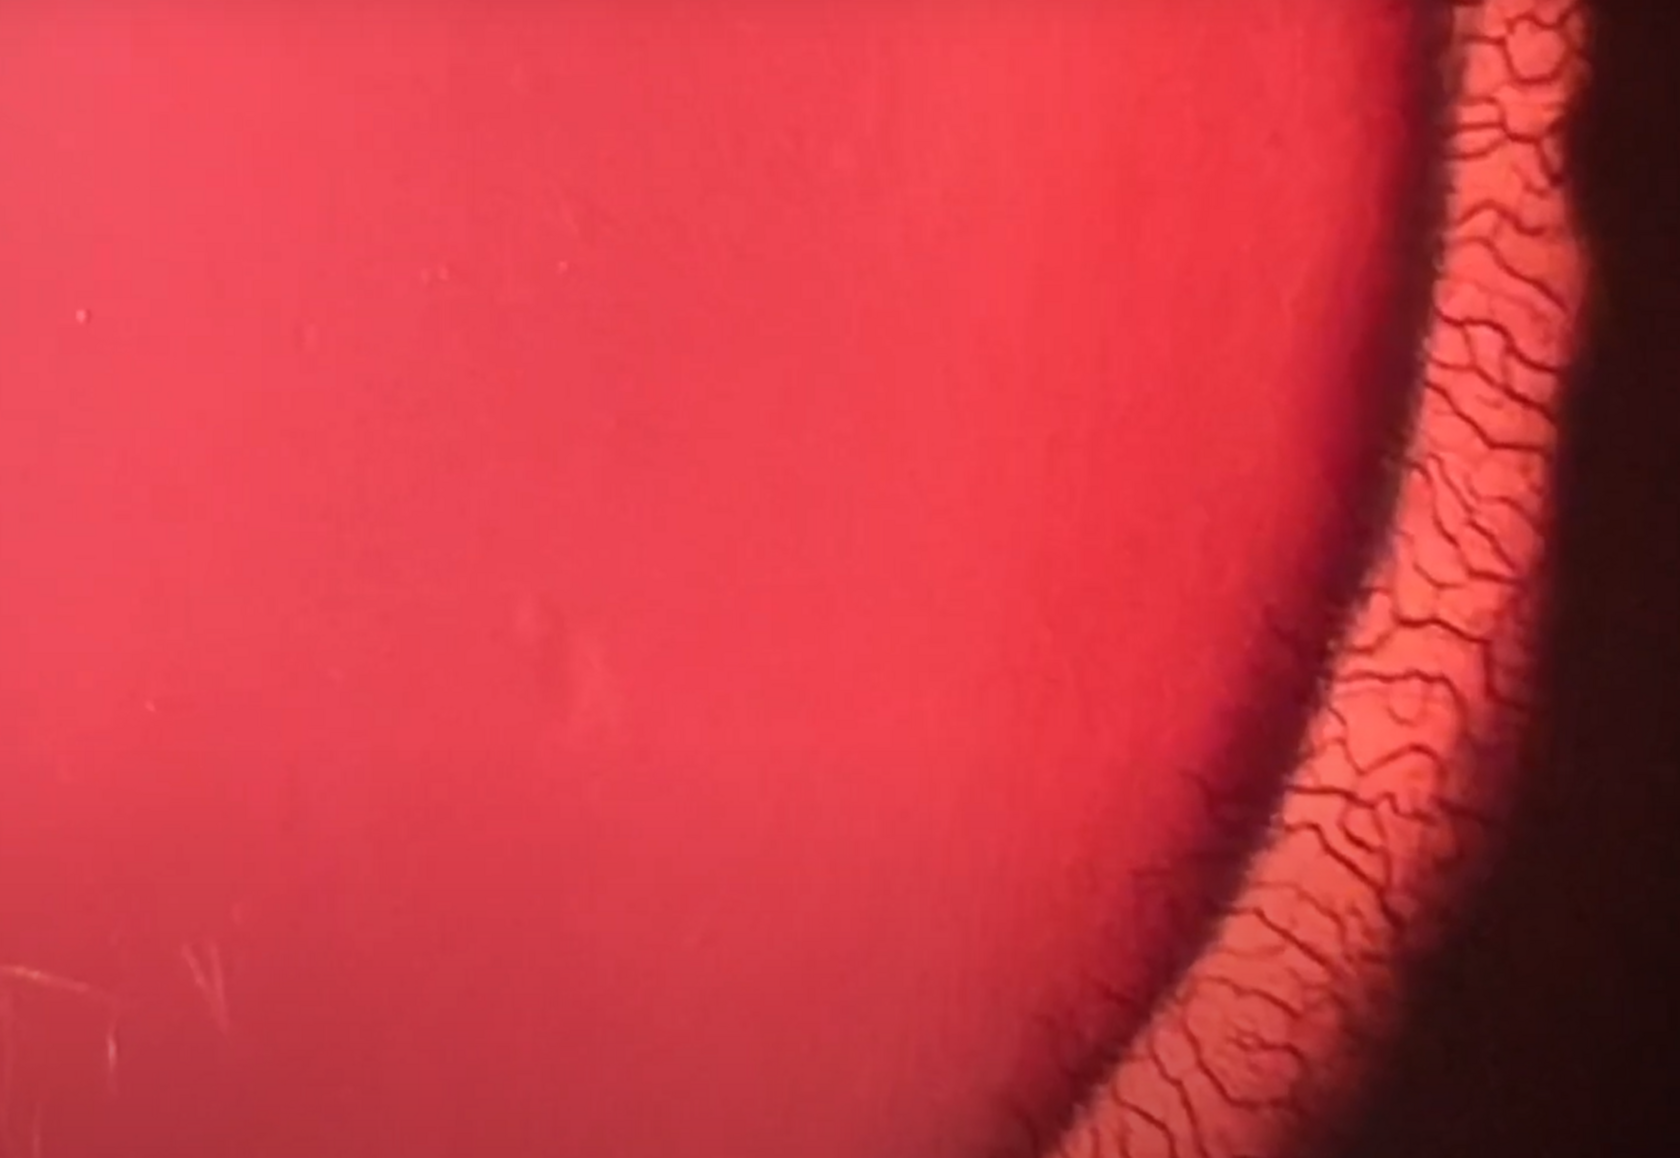

Как видит человек, у которого нет бинокулярного зрения?

Уважаемые друзья, на сайте появилось новое видео, в котором я рассказываю, как видит человек без бинокулярного зрения. Родители очень беспокоятся о его наличии, но не понимают до конца, что значит его наличие или отсутствие. Для подродного объяснения я начал с того, что немного углубился в эволюцию, чтобы рассказать, какие именно причины появления бинокулярного зрения у человека. Надеюсь, видео окажется для вас интересным. Видео вошло в курс «Дальнозоркость, амблиопия. Курс для родителей» и доступно для тех, у кого есть подписка на 12 месяцев.